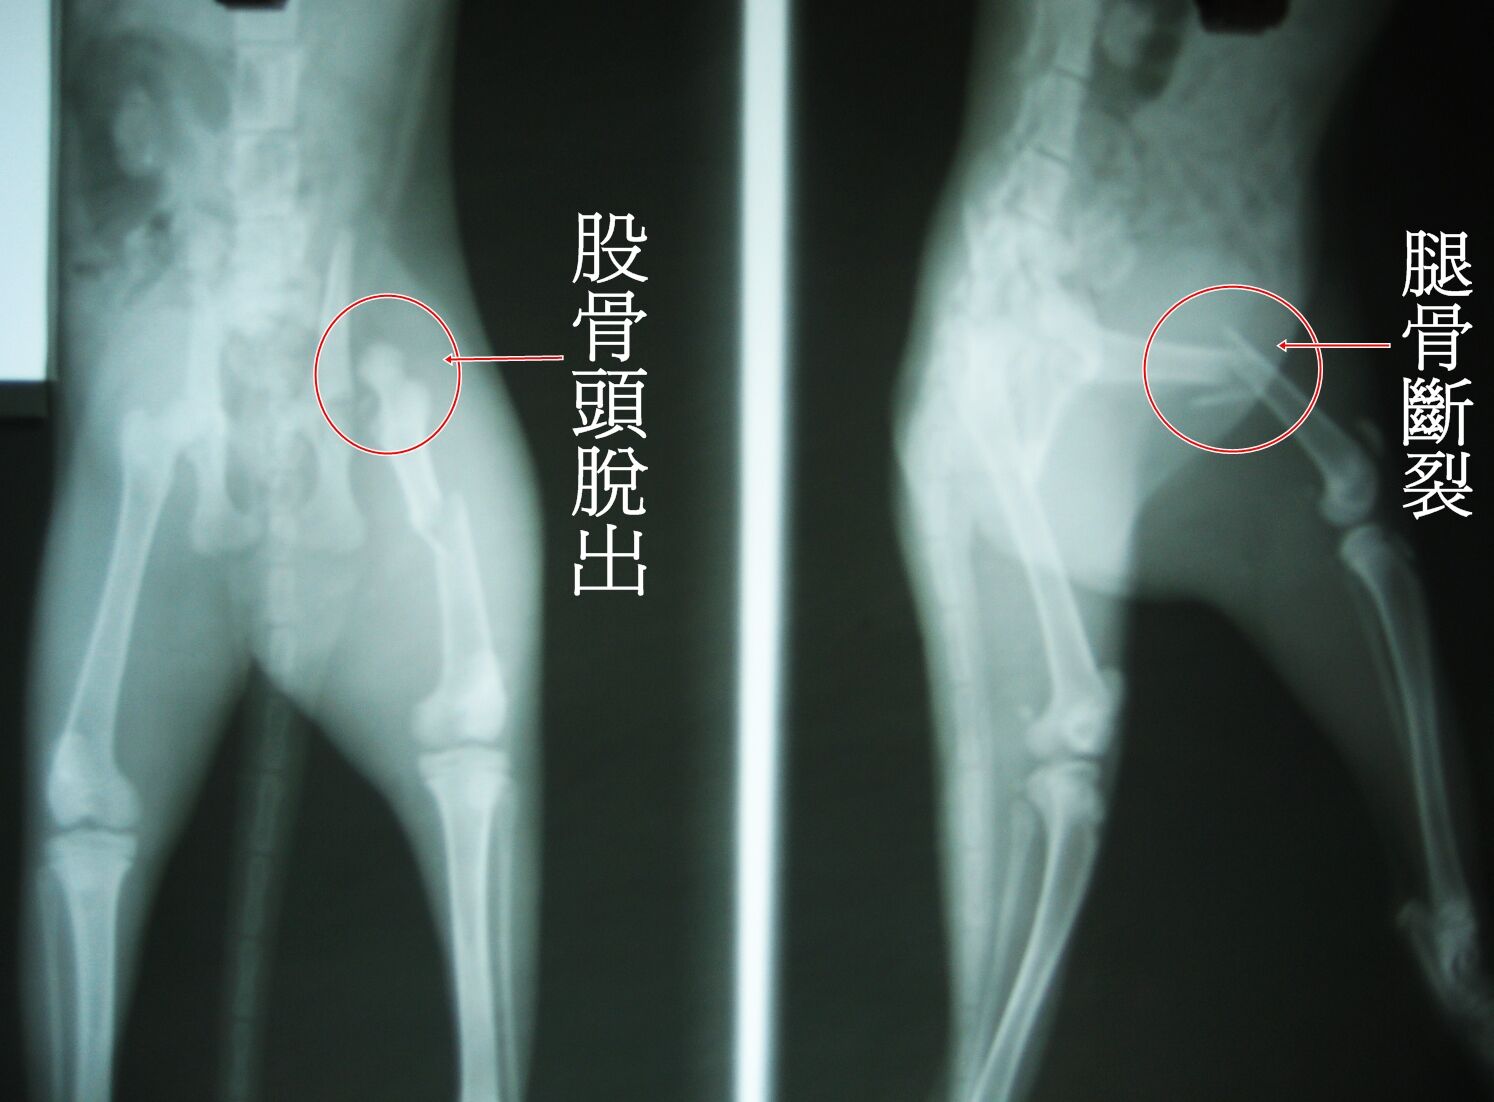

我用外套包起連忙送去醫院,醫生也緊急拍了X光檢查,發現小貓腿骨斷裂,股骨向上穿刺,膀胱也擠到腹腔造成赫尼亞。

手術分了2次進行。第一次動了腿骨骨折修復及股骨切除的部份,第2次修補腹腔赫尼亞。我問醫師為何不一次完成,醫生說,腿骨修復手術就花了好久的時間才完成,再加上貓咪年繼很小,太久的手術對貓咪來說是種風險,所以才分2次進行。